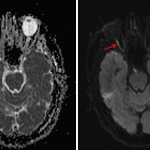

- Restricted diffusion in the anterior intraorbital right optic nerve with associated signal hyperintensity on STIR

- Ischemic optic neuropathy

Findings concerning for ischemic right optic neuropathy. Recommend ophthalmology evaluation.